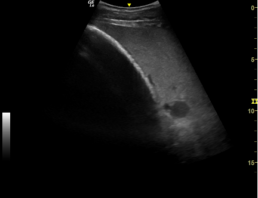

Wandverdickter Dünndarm dargestellt von unten, deutlich vermehrt freie Flüssigkeit im Bauchraum